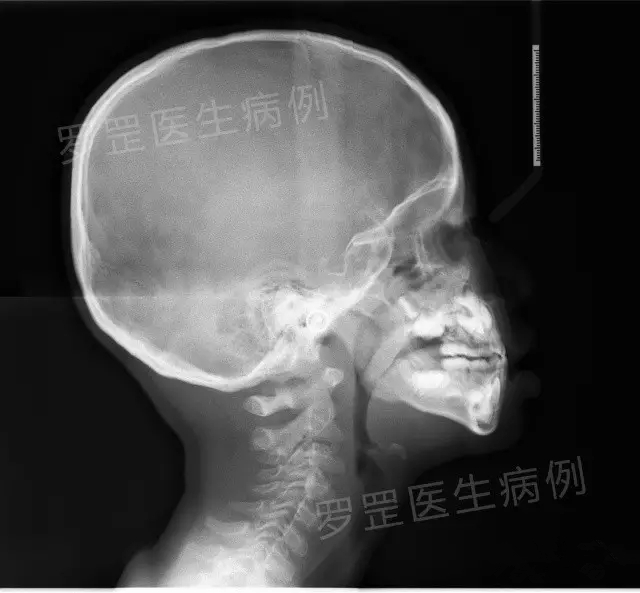

2.拍片

(头颅侧位片)

如果家长选择了某种情势,医森初诊当天会安排助手给小朋友拍摄口腔全景片&头颅侧位片,可以更加准确了解小朋友牙齿生长发育情况及骨骼发展情况,以便更好制定正畸方案。